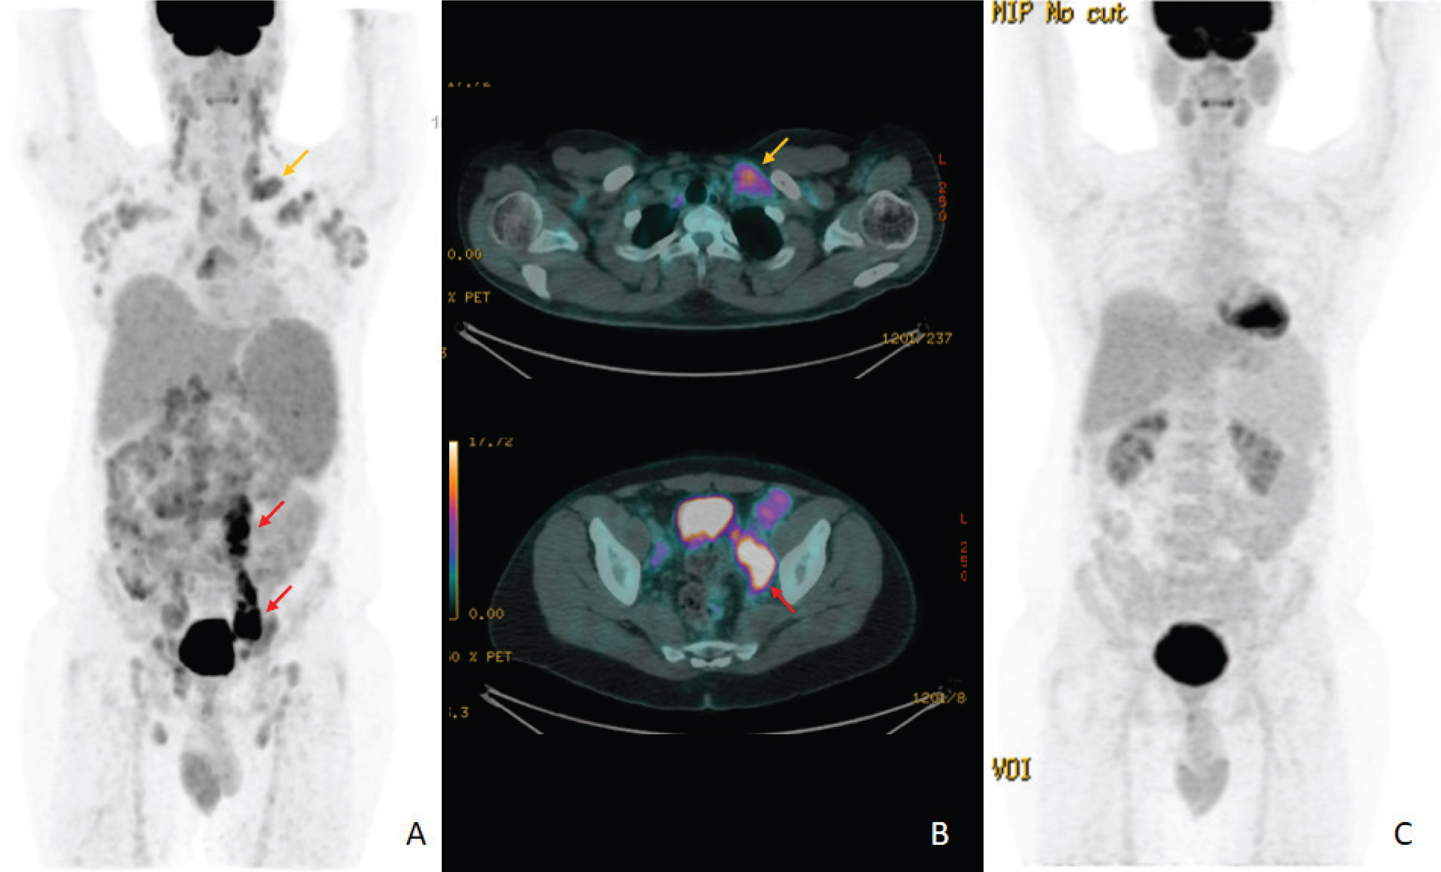

The histological diagnosis of FL is made according to the Saudi Lymphoma Group’s Clinical Practice Guidelines for Diagnosis, Management and Follow-up (34,40). Briefly, histological grading is made according to the the presence of centroblast (cB) per high-power field (HPF): grade 1 (0-5 cB per HPF), grade 2 (6-15 cB per HPF), grade 3A (>15 cB per HPF, cB with intermingled centrocytes), and grade 3B (>15 cB per HPF, pure sheets of blasts) (34). An example of different histology in FL patient is shown in Figure 3. The modern hybrid imaging diagnostic modality with PET/CT in a single-shot scan (41) is the recommended diagnostic tool to detect nodal and extranodal disease (1,42). Moreover, a PET/CT is essential to plan involved-site radiotherapy (ISRT) (43). An example of PET/CT before and after treatment in a FL patient is shown in Figure 4.

Fig 4

Figure 4. Follicular lymphoma with transformation. A 38-year-old male presented with follicular lymphoma. A, His initial PET/CT showed multiple involved nodes above and below the diaphragm showing moderate FDG uptake. Number of significantly avid nodes seen in the left para-aortic region extending down to the left pelvis, in keeping with transformation. B, Orange arrows show uptake in a left supraclavicular node with an SUVmax of 5. Red arrows show uptake in left para-aortic and pelvic nodes with SUVmax values of up to 11. C, Follow-up PET/CT after treatment showed a complete metabolic response (Images courtesy of Saeed Shieban).